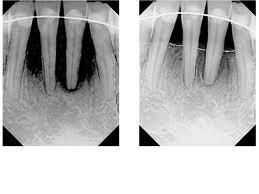

One of the serious areas it failed to deal with is the diet sodas, which so many people opt for in place of regular soda thinking they are doing a good thing.and that it helps them keep down the pounds, however, the science shows that artificial sweeteners are hundreds to thousands of times sweeter than regular sugar. This causes your body to think that the sugar is coming, and actually pump out insulin which causes more body fat, at the same time it causes your metabolism to slow down. Don’t forget that all of the acids and sugars are all the while eating away your teeth and causing decay and periodontal problems. There is no getting around it sugar is a drug, in whatever form, and is very harmful to your teeth and the entire rest of your body.